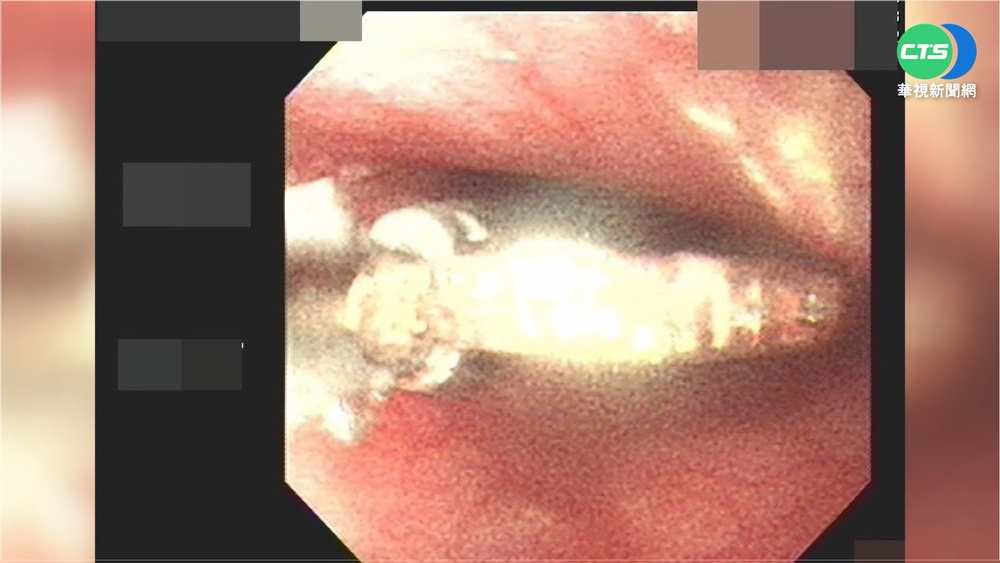

鮮魚料理上桌,怎能不吃一口,但高雄一名婦人因為不小心吞入魚刺,差點致命,一根2.3公分長長魚刺直接穿破食道,插進左側甲狀腺裡,義大醫院耳鼻喉部耳科主任王建忠說:「這三角形是正常的甲狀腺,左邊這個腫起來的東西。」婦人誤吞魚刺直到10天過去,脖子越來越痛,才去就醫,醫師找遍食道咽喉都找不到,後來才發現早在體內游走移位。